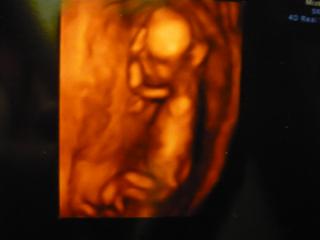

Ahoj holky, ještě přidávám fotečku z pondělního UTZ.. Normálně je to buclík, tady ale vypadá, že ani nedostává najíst 🙂.

@petinkas jééé to je malinkatý ještě 🙂 jak si tam bucá spokojeně 🙂

@petinkas To je krááásný 🙂 Taky máme 3D fotečku a je to strašně hubenoučký takový jako malá opička 😀 ale je to krááásný, uplně něco jinýho vid ? 🙂 🙂

@hanickaa.d náhodou už skoro 8 cm 🙂 - velikost kreditní karty.. 🙂

@barbulinka1 přesně.. mamka říkala jak králíček 🙂.. taky mi přijde, že je to úplně něco jiného - takového skutečnějšího.. jak mi ani nebylo špatně, tak jsem si vůbec nepřipadala těhotně, ale když to vidíš v tom 3D - je to změna..

@petinkas Babička zase když tu fotku viděla, tak říkala, že je to jak kůzlátko 😀 😀 ale je to krásný a je to uplně něco jinýho, než normální ultrazvuk 🙂 🙂 už se těšim až pak pujdeme na 3D, sice si zase připlatíme, jako za screening, ale věřim, že to bude stát za to 🙂